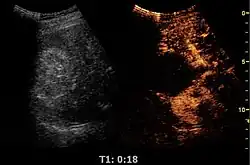

Contrast-enhanced renal ultrasonograph, showing a renal cell carcinoma successfully treated with thermal ablation, as no contrast enhancement is seen[1]